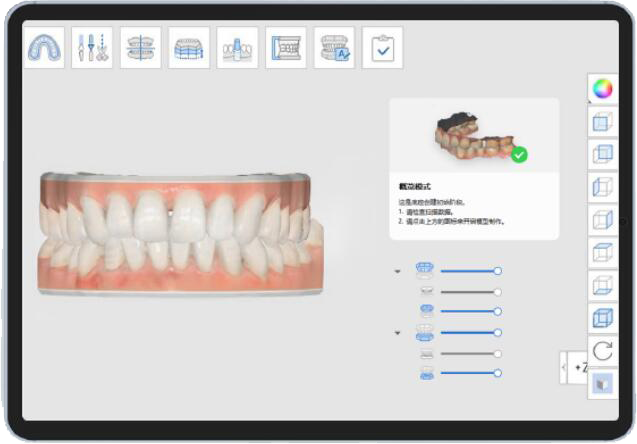

基于个性化矫治方案定制且可拆装的透明矫治器

数字化辅助案例评估支持及矫治方案

力学模拟系统

云服务数据平台移动和PC端交互服务系统

数据分析更专业

治疗方案更精准

矫治效果更可控

用户体验更舒适便捷

数字化

可视化

新一代高分子材料,生产可抑菌的隐形矫治器膜片,且同时具备良好弹性、韧性和控制力,能有效控制长期使用的矫治力衰减,精准实现矫治力,缩短矫治周期,矫治更舒适,适应症更广泛。

工艺领先:全程数字可视化工艺流程、十万级无菌无尘净化车间。

品质保障:采用全球UDI数字身份追溯系统,中国人保产品质量险承保。